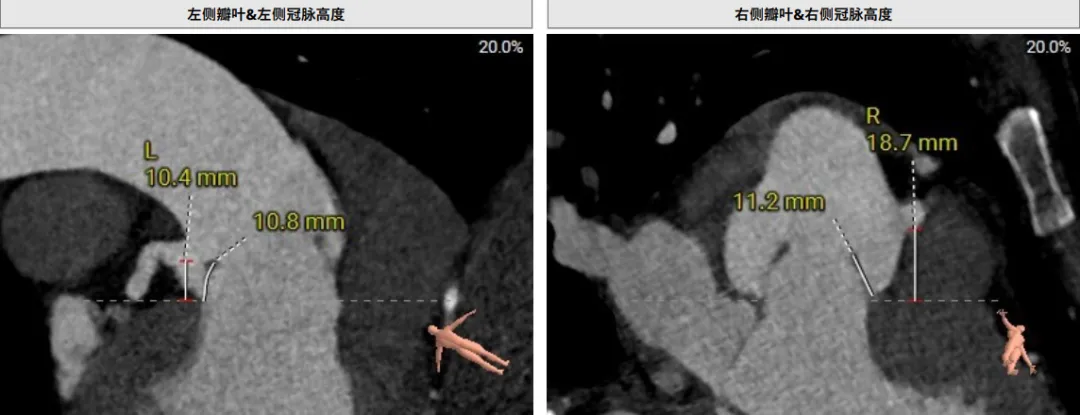

该患者术前CT评估提示:主动脉瓣Type-I型,瓣叶稍增厚,左右冠窦瓣叶交界粘连,无冠窦瓣叶轻微钙化,存在三个瓣窦,分布不均匀,左右冠窦融合;主动脉瓣环周长折算直径32.6mm;左心室流出道周长折算直径32.0mm,无钙化,无狭窄;STJ直径36.2mm,升主动脉直径38.6mm;左侧冠脉10.4mm ,瓣叶长10.8mm;右侧冠脉18.7mm,瓣叶长11.2mm;双侧冠脉开口高度可,无钙化;心尖-主动脉夹角偏大,左室主动脉夹角为120°;